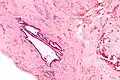

Endosalpingiosis is diagnosed by a pathologist on excision (e.g. biopsy).

It is characterized by cysts with tubal-type epithelium (e.g. ciliated epithelium) surrounded by a fibrous stroma. It is not often associated with hemorrhage.

Endosalpingiosis is occasionally found in lymph nodes, and may be misinterpreted as an adenocarcinoma metastasis.[6]

Intermed. mag.

High mag.

Very high mag.